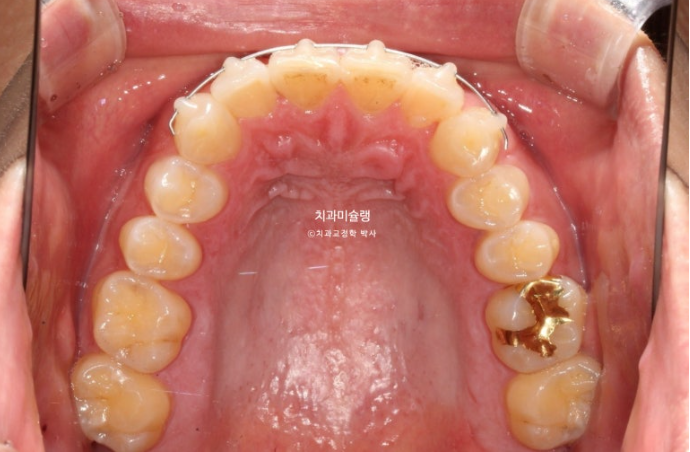

25.08

치료시작 4개월차 모습입니다.

윗니배열은 완벽하며

아랫니 배열이 조금 부족합니다.